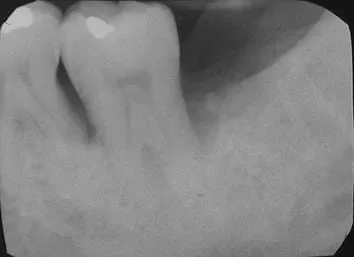

治療後9個月

原先牙齦腫痛化膿的症狀已消失, 以放射線檢查追蹤,患處骨密度增加,顯示牙周再生良好。

( 圖1: 術後9個月)